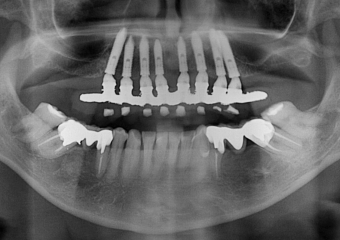

Raio X com a prótese fixa em resina, sobre implantes Cone Morse